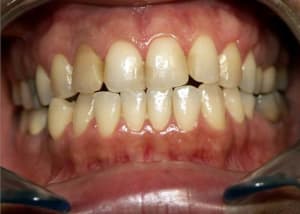

Cas_3_a_mascgd.jpg

Voir le message contenant cette image